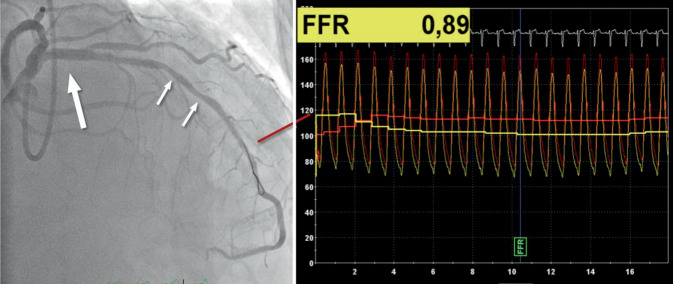

In der Leitlinie werden ein Stenosegrad >50 % der LAD sowie ein Ischämieareal >10 % als prognostisch relevant eingestuft, was jedoch durch die kürzlich publizierte ISCHEMIA-Studie infrage gestellt wird [63]. In allen Fällen mit einem Stenosegrad <90 % muss der Nachweis einer Ischämie durch nichtinvasive Untersuchungen erbracht werden bzw. eine positive iFR/RFR/DFR/FFR-Messung vorliegen.